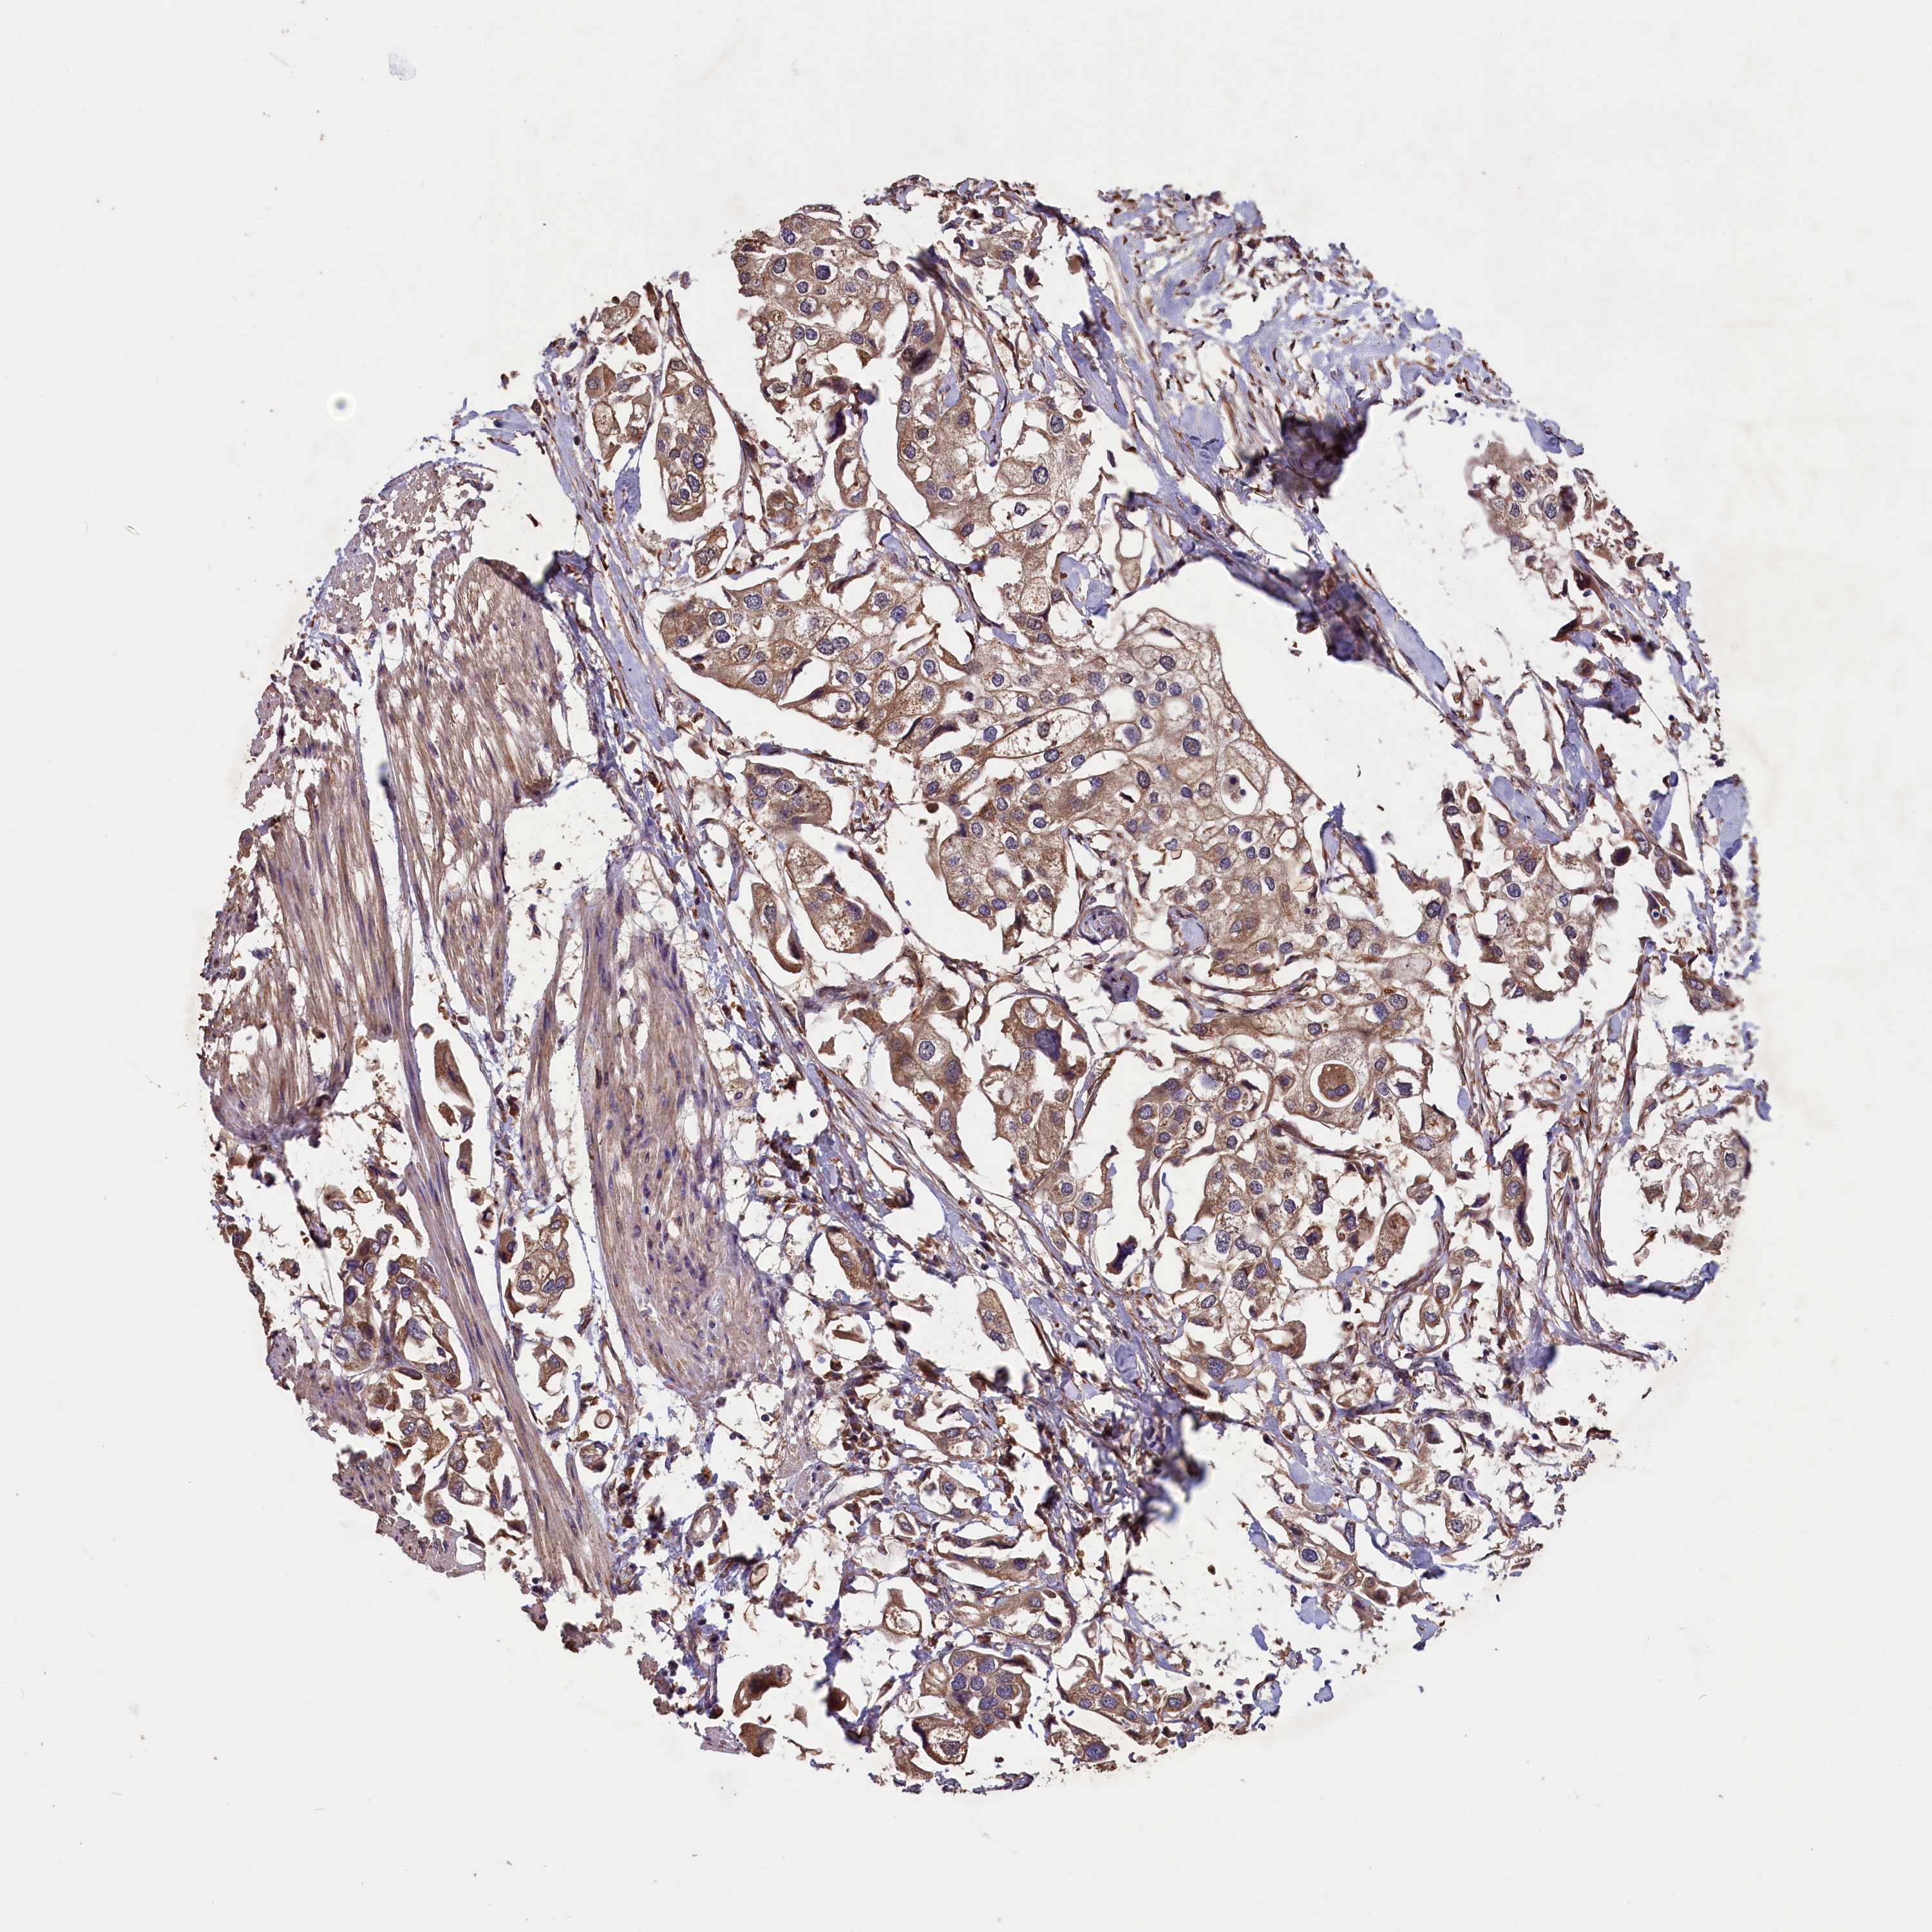

UROTHELIAL CANCER - Protein expressioni

A mouse-over function shows sample information and annotation data. Click on an image to view it in a full screen mode. Samples can be filtered based on level of antibody staining by selecting one or several of the following categories: high, medium, low and not detected. The assay and annotation is described here.

Note that samples used for immunohistochemistry by the Human Protein Atlas do not correspond to samples in the TCGA dataset.

Antibody stainingi

Antibody staining in the annotated cell types in the current human tissue is reported as not detected, low, medium, or high, based on conventional immunohistochemistry profiling in selected tissues. This score is based on the combination of the staining intensity and fraction of stained cells.

Each image is clickable and will lead to virtual microscopy that enables deeper exploration of all samples and also displays staining intensity scores, fraction scores and subcellular localization as well as patient and tissue information for each sample.

Antibody HPA041647

Antibody HPA044218

Staining

High

Medium

Low

Not detected

Intensity

Strong

Moderate

Weak

Negative

Quantity

>75%

75%-25%

<25%

None

Location

Nuclear

Cytoplasmic/membranous

Cytoplasmic/membranous,nuclear

Urothelial carcinoma, High grade

Urothelial carcinoma, Low grade